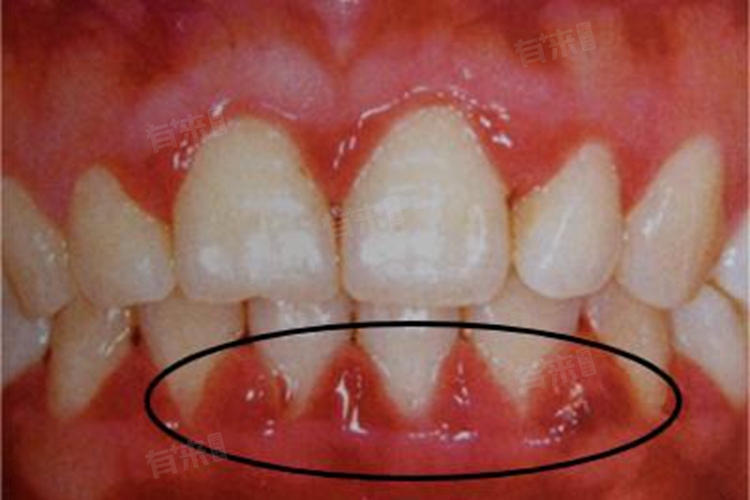

5、妊娠期龈瘤:部分孕妇在妊娠期间可能会出现牙龈瘤样增生物,称为妊娠期龈瘤,通常是由于局部刺激因素,如牙菌斑、牙石、不良修复体等,与激素水平变化共同作用的结果。一般建议在分娩后进行手术切除,在孕期,可通过加强口腔卫生和局部冲洗等方法控制其生长和症状。